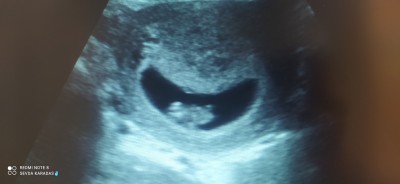

Kızlar sizce bebegimin cinsiyeti nedir 8+4haftalik

Gebelik haftası 8+4